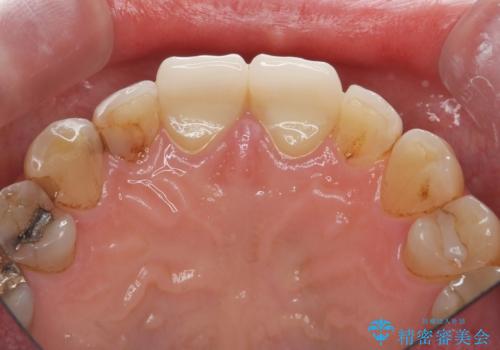

- 前歯の小さな虫歯を複数回治療した結果、つぎはぎだらけになってしまい審美的な改善を求めて来院されました。

これ以上のコンポジットレジン修復は更なる審美障害を招きかねないので、全体を覆うセラミッククラウンを選択します。

ディープバイト・噛み合わせが強いことからフルジルコニアクラウンを選択しました。